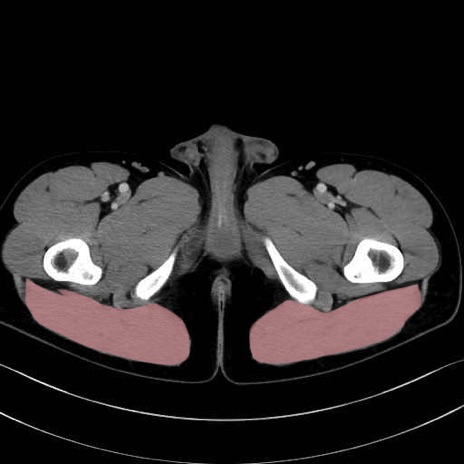

大殿筋 (Gluteus maximus)